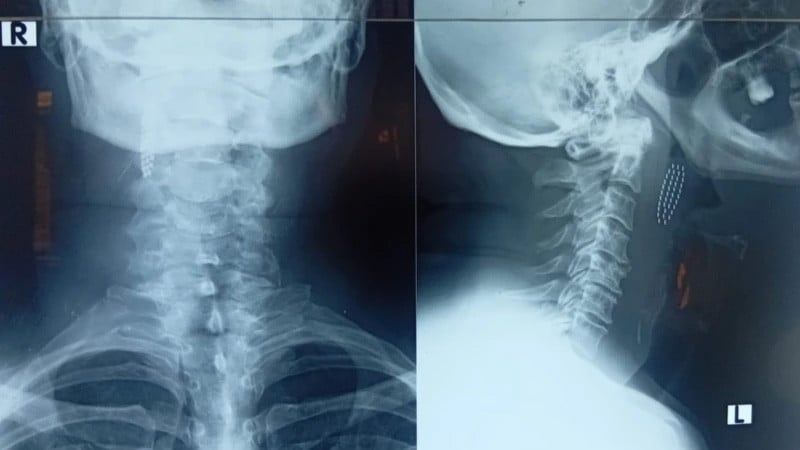

پریم لال کے مطابق وہ فوری طور پر قریبی نجی اور پھر سرکاری اسپتال پہنچے، مگر ابتدا میں ڈاکٹروں کو ٹوتھ برش کا ٹوٹا ہوا حصہ تلاش کرنے میں مشکل پیش آئی۔ ایک گھنٹے کے اندر اندر ان کی حالت بگڑنے لگی، گلا بند ہونے لگا اور کھانسی کے ساتھ خون آنے لگا، جس کے بعد ایکسرے اور سی ٹی اسکین میں واضح ہوا کہ برش کا حصہ اندر ہی موجود ہے۔

بعد ازاں پریم لال کو گال شہر کے سرکاری اسپتال منتقل کیا گیا جہاں کان، ناک اور گلے کے ماہرین کی نگرانی میں ایک پیچیدہ آپریشن کیا گیا۔ ڈاکٹروں کے مطابق برش کا ٹکڑا حلق کو زخمی کرتے ہوئے ایک بڑی شریان کے قریب جا رکا تھا، جو انتہائی خطرناک صورتحال تھی۔ کئی گھنٹوں کی جدوجہد کے بعد سرجری کامیاب رہی اور برش کا ٹکڑا نکال لیا گیا۔